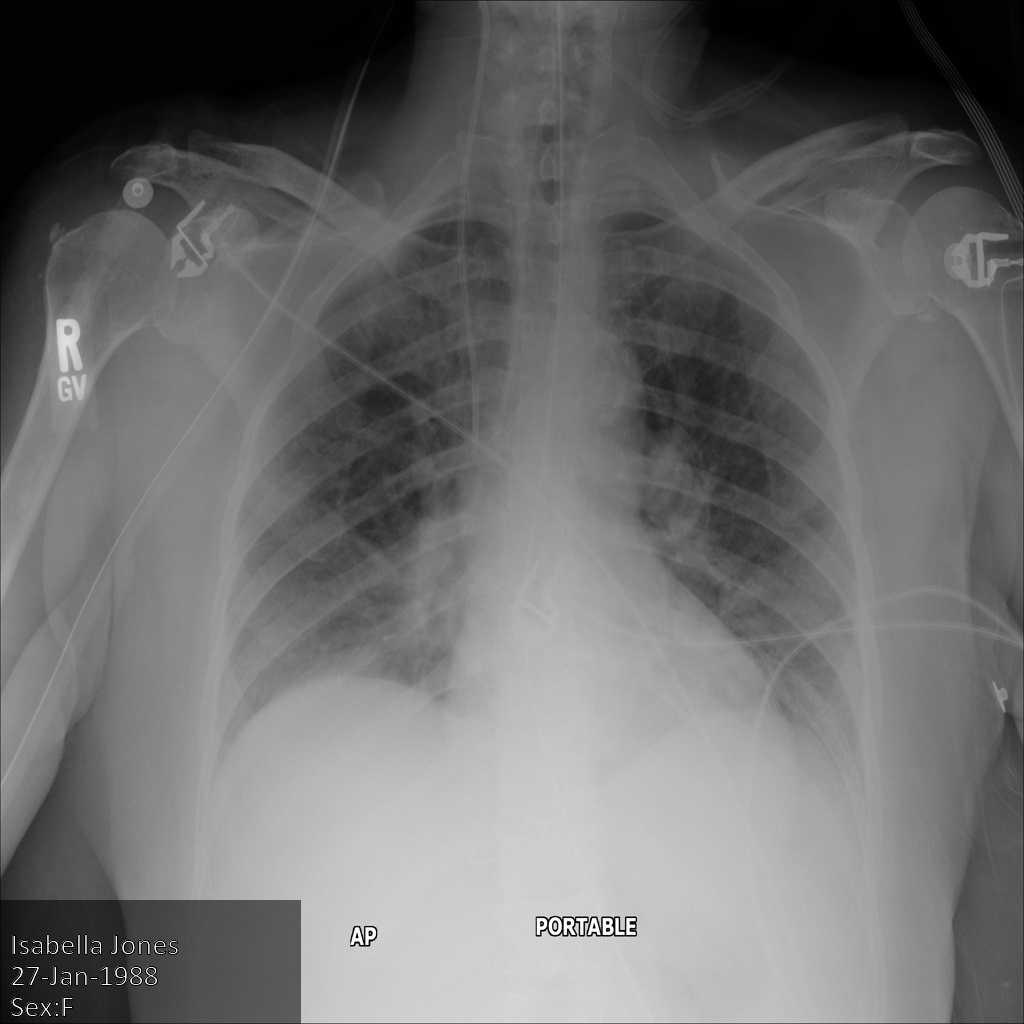

L'image suivante montre une radiographie non masquée d'un patient :

xray2_unredacted

Une fois l'image envoyée à l'API Cloud Healthcare à l'aide de l'option REDACT_SENSITIVE_TEXT, elle apparaît comme suit :

xray2_redact_sensitive_text

Vous pouvez constater que les événements suivants se sont produits :

• Le paramètre PERSON_NAME en bas à gauche de l'image a été masqué.

• Le paramètre DATE en bas à gauche de l'image a été masqué.

Le sexe du patient n'a pas été masqué, car il n'est pas considéré comme du texte sensible selon le paramètre infoTypes DICOM par défaut.